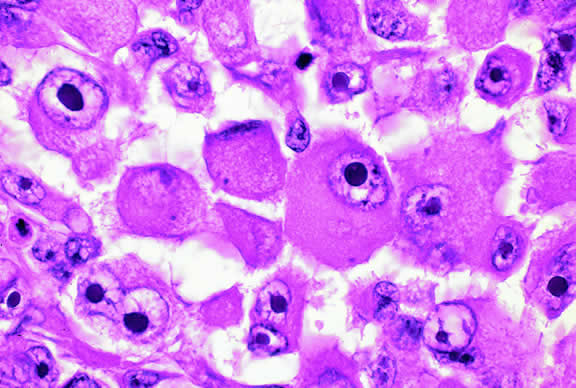

Epithelioid melanoma cells comprise the poorly differentiated end of the cytologic spectrum. Melanomas that contain epithelioid cells have a poorer prognosis. The term epithelioid meaning epithelial-like reflects the fanciful resemblance of the tumor cells to the cells of simple epithelia. Epithelioid cells have abundant cytoplasm and are often polygonal in shape (Fig. 33). They have distinct cytoplasmic margins, are poorly cohesive, and do not grow as a syncytium. The nuclei of epithelioid cells are usually round or oval and often appear vesicular because of margination or clumping of the chromatin along the inner side of the nuclear membrane. Epithelioid melanoma cells also have prominent nucleoli that are often large and reddish purple. Variants of epithelioid cells include relatively uniform small epithelioid cells (Fig. 34) and bizarre tumor giant cells that may appear wildly anaplastic (Fig. 35).

Fig. 33. Epithelioid melanoma cells. The cytoplasmic margins of these large, poorly cohesive epithelioid melanoma cells are easily discernible. Epithelioid cell nuclei are typically round and have peripheral margination of coarsely clumped chromatin. Epithelioid cells usually have prominent reddish purple nucleoli. They typically are polyhedral in shape and have copious amounts of cytoplasm. (Hematoxylin-eosin, × 250.)

Fig. 34. Small epithelioid cells. Cells are relatively small but are definitely epithelioid in character. They are polyhedral in shape and have distinct cytoplasmic outlines. The round nuclei contain prominent nucleoli. (Hematoxylin-eosin, × 250.)

Fig. 35. Tumor giant cell, uveal melanoma. Tumor giant cells are highly anaplastic epithelioid cells. They are relatively rare, and their prognostic significance is uncertain. (Hematoxylin-eosin, × 100.)

Melanoma cells should be classified by their nuclear characteristics. Spindle-shaped cells that have epithelioid nuclei occasionally are encountered; such cells are classified as epithelioid. In recent years, the term intermediate cell has been used increasingly. Intermediate cells are cells that have nuclear characteristics that are intermediate between spindle B and epithelioid. For example, one might apply the term intermediate cell to a spindle B cell that has a nucleus that is somewhat large and has a fairly prominent nucleolus.